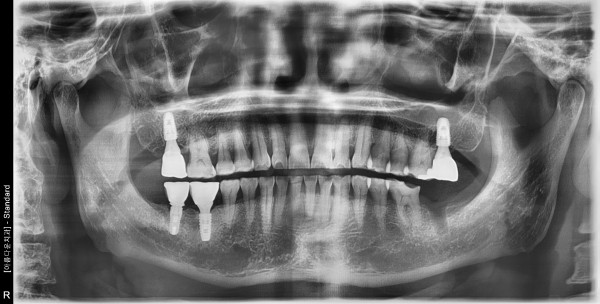

▶71세 남자 임플란트 재수술